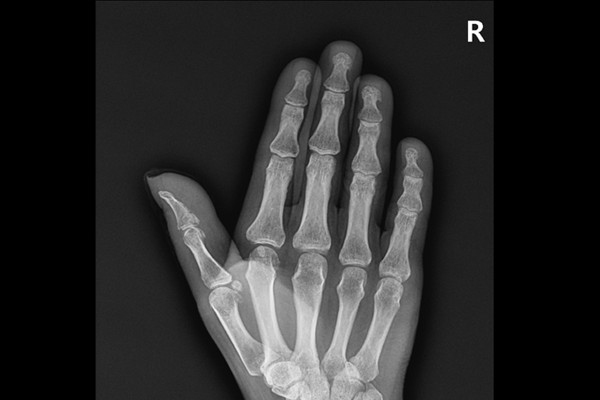

타병원에서 촬영한 X-RAY를 보면 골절로 인한 뼛조각이 확인됩니다.

CT영상을 확인했을 때 역시 뼛조각이 확인되며, 원래 있어야 할 위치에서 떨어져 내려와 있는 것이 확인되어 손가락 안들림, 엄지 망치수지 골절(Open mallet Fx. 1st DP base hand Rt.)을 진단하였습니다.